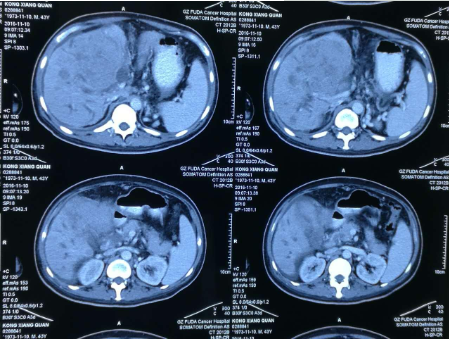

孔祥泉,男性,43岁,因皮肤发黄、肝区不适一个月,各种检查结果很不乐观。MR检查见:“S4/8肝内多发结节及团块(最大102mm*81mm),考虑肝癌合并子灶,侵犯肝门区胆管,门静脉主干及分支、肝右静脉受压、管腔变窄,肝内胆管扩张。胆囊增大并壁周水肿。肝硬化、脾大、少量腹水,食管下段、胃底及脾周静脉曲张,肝门区、门腔间隙及腹主动脉旁淋巴结(百度搜索:广州复大肿瘤医院)。

看到了希望,孔祥泉继续坚持中药调理。两个月之后,孔祥泉再次复诊,他感觉良好,说自己能够每天开车100多公里路往返东莞的公司上班,兴高采烈地说自己恢复正常了!并且实验室检查结果也显示,除了AFP增高之外,其他指标都基本正常。看到这样的结果,我们科所有的人都替他感到高兴!

确诊晚期肝癌的孔祥泉先生,从徐院长给他实施中药治疗到现在,存活了整整十个月,远远超过当初中山大学附属肿瘤医院预计的三个月的生命期限。最重要的是现在病人精神状态和自我感觉都很好,可以正常工作,各项生化指标基本都趋于稳定。